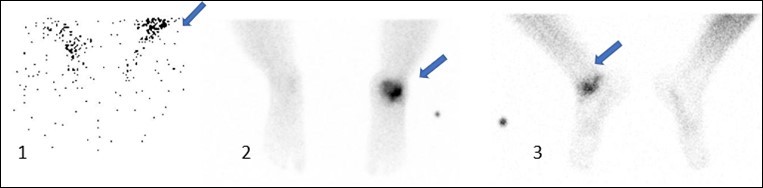

Three phase Bone scan : Increased flow (1) indicates preserved blood supply to graft region along with increased blood pooling in the (2) image with spot (3) at delayed 3hr reveals increased tracer uptake ascertaining the integrity and viability of the bone allograft